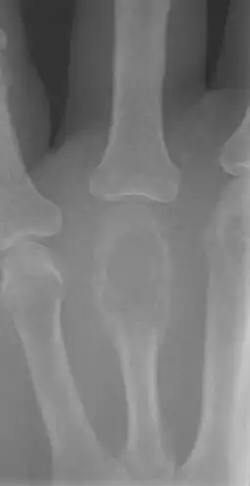

Diagnosis is generally by X-ray and other radiological tests such as CT scan, MRI, PET scan and bone scintigraphy.[1] Blood tests might include a complete blood count, inflammatory markers, serum electrophoresis, PSA, kidney function and liver function.[1] Urine may be tested for Bence Jones protein.[1] For confirmation of diagnosis, a biopsy for histological evaluation might be required.[1]

A bone tumour may be felt on examination, following which a plain X-ray is usually carried out.[1][15] Blood tests might include a complete blood count, inflammatory markers, serum electrophoresis, PSA, kidney function and liver function.[1] Urine may be sent for Bence Jones protein.[1] Other tests that might be requested include a CT scan, MRI, PET scan and bone scintigraphy. For confirmation of diagnosis, a biopsy for histological evaluation might be required, using either a needle or by incision (open biopsy).[1][2]